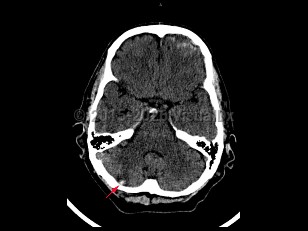

Imaging Studies image of Cerebellar contusion - imageId=7872512. Click to open in gallery.  caption: '<span>Axial CT image demonstrates a  focal hyperdensity in the right cerebellum with surrounding edema in  this patient with history of trauma. Findings were consistent with  cerebellar contusion.</span>'

Axial CT image demonstrates a focal hyperdensity in the right cerebellum with surrounding edema in this patient with history of trauma. Findings were consistent with cerebellar contusion.